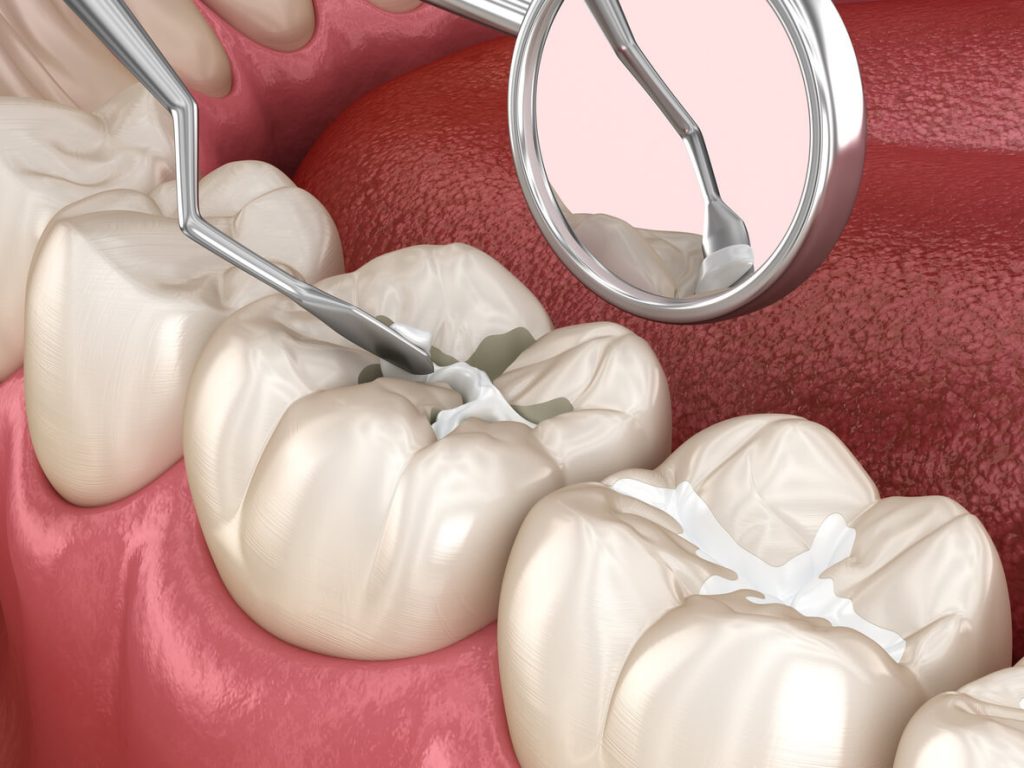

Endodoncia

Salvamos dientes dañados o infectados gracias a tratamientos conservadores de alta precisión.